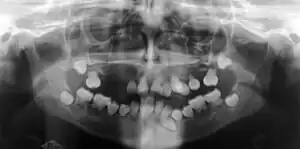

| Preoperative panoramic radiographs showing features of dentin dysplasia type I | |

Radiographic feature

In other words, affected primary teeth usually have abnormal shaped or shorter than normal roots. “Crescent/half-moon shaped” pulp chamber remnant in permanent teeth can be seen on x-rays. The roots may appear to be darker or radiolucent/pointy and short with apical constriction. Dentine is laid down abnormally and causes excessive growth within the pulp chamber. This will reduce the pulp space and eventually cause incomplete and total pulp chamber obliteration in permanent teeth.[12][13] Sometimes periapical pathology or cysts can be seen around the root apex.[11] Most cases of DD associated with peri-apical radiolucency/ pathology have been diagnosed as radicular cysts, but some of them have been as diagnosed peri-apical grauloma instead.[14]